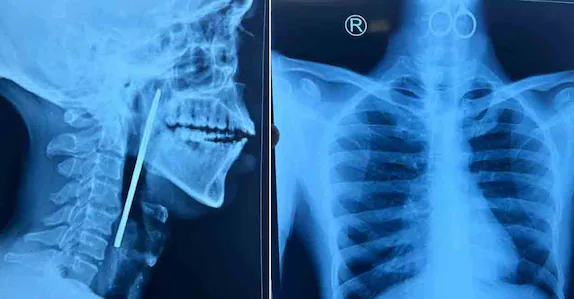

കോഴിക്കോട് ∙ ഗവ. മാനസികാരോഗ്യ കേന്ദ്രത്തിലെ രോഗി വിഴുങ്ങിയ കത്രിക ഗവ. മെഡിക്കൽ കോളജ് ആശുപത്രിയിൽ നടത്തിയ ശസ്ത്രക്രിയയിലൂടെ പുറത്തെടുത്തു. ഭക്ഷണം കഴിക്കാത്തതിനെ തുടർന്ന് തിങ്കളാഴ്ച വൈകിട്ടാണ് യുവാവിനെ അത്യാഹിത വിഭാഗത്തിൽ പ്രവേശിപ്പിച്ചത്. അന്നനാളത്തിൽ കത്രിക കുടുങ്ങി കിടക്കുന്നതായി എക്സറേ പരിശോധനയിൽ കണ്ടെത്തി. തുടർന്ന് രോഗിയെ ഇഎൻടി വിഭാഗത്തിൽ പ്രവേശിപ്പിച്ചു.

തിങ്കളാഴ്ച രാത്രി നടത്തിയ അടിയന്തിര ശസ്ത്രക്രിയയിലൂടെയാണ് 15 സെന്റിമീറ്ററോളം നീളമുള്ള കത്രിക പുറത്തെടുത്തത്. ഇഎൻടി വിഭാഗത്തിലെ ഡോ. ശ്രീജിത്ത്, ഡോ. നിഖിൽ, ഡോ. ചിത്ര, ഡോ. ഫാത്തിമ, ഡോ. ആഷ്, അനസ്തീസിയ വിഭാഗത്തിലെ ഡോ. മിനു, ഡോ. ധന്യ, ഡോ. ഫഹ്മിദ, ഡോ. രാഗിൻ എന്നിവരാണ ശസ്ത്രക്രിയ സംഘത്തിലുണ്ടായിരുന്നത്. രോഗിയുടെ ആരോഗ്യനില തൃപ്തികരമാണെന്ന് ആശുപത്രി അധികൃതർ പറഞ്ഞു.